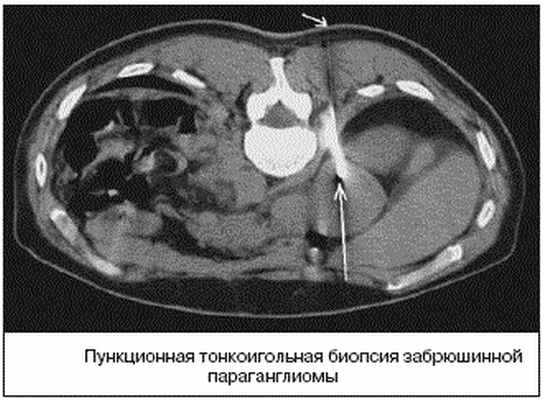

В случае забрюшинних неорганных опухолях обязательно выполняют биопсию для цитологического и гистологического исследований. Чрезкожную аспирационную пункционную биопсию осуществляют в случае расположения забрюшинной опухоли на боковых стенках таза. В случае тазового расположения опухоли применяют пункционную биопсию через заднюю стенку влагалища или путем прокола ишиоректального участка. Помогают проводить прицельную биопсию эхография и компьютерная томография.

Пункционная биопсия позволяет уточнить характер процесса и определить морфологическое строение новообразования. Чаще пункционная биопсия является завершающим этапом обследования больного после уточнения локализации, размеров и взаимоотношения опухоли с соседними органами.